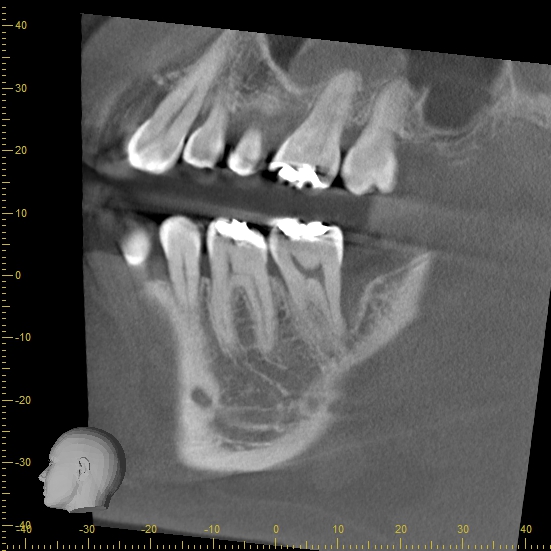

歯周病が進行すると、歯を支える骨が失われていきます。骨の様子を確かめるために、X線検査を行います。

当院のX線検査は、「CT」を使います。CTはお口の周囲を360度回転しながら撮影するので、二次元の影像を撮影するレントゲンに比べて、立体的で鮮明な映像が得られます。

6番遠心に出血と排膿があり、CTより2・3壁性の骨欠損を認めたため、再生療法の適応症と判断し歯周基本治療後に歯周外科を行った症例

他院にて保存不可能と言われたため、セカンドオピニオンでご来院。

7番遠心の骨欠損は大きく、再生療法は難しい症例だが、CT画像より骨欠損は根尖には達しておらず、

患者さんの歯を残したいとの希望もあったため再生療法を行った症例